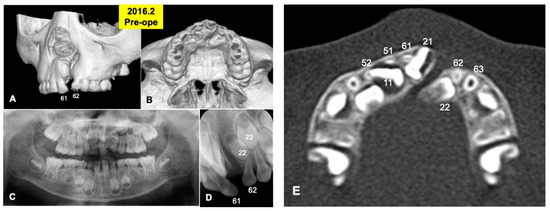

2.5. Radiographic Evaluation

Gross View and Radiographic Evaluation after Surgery